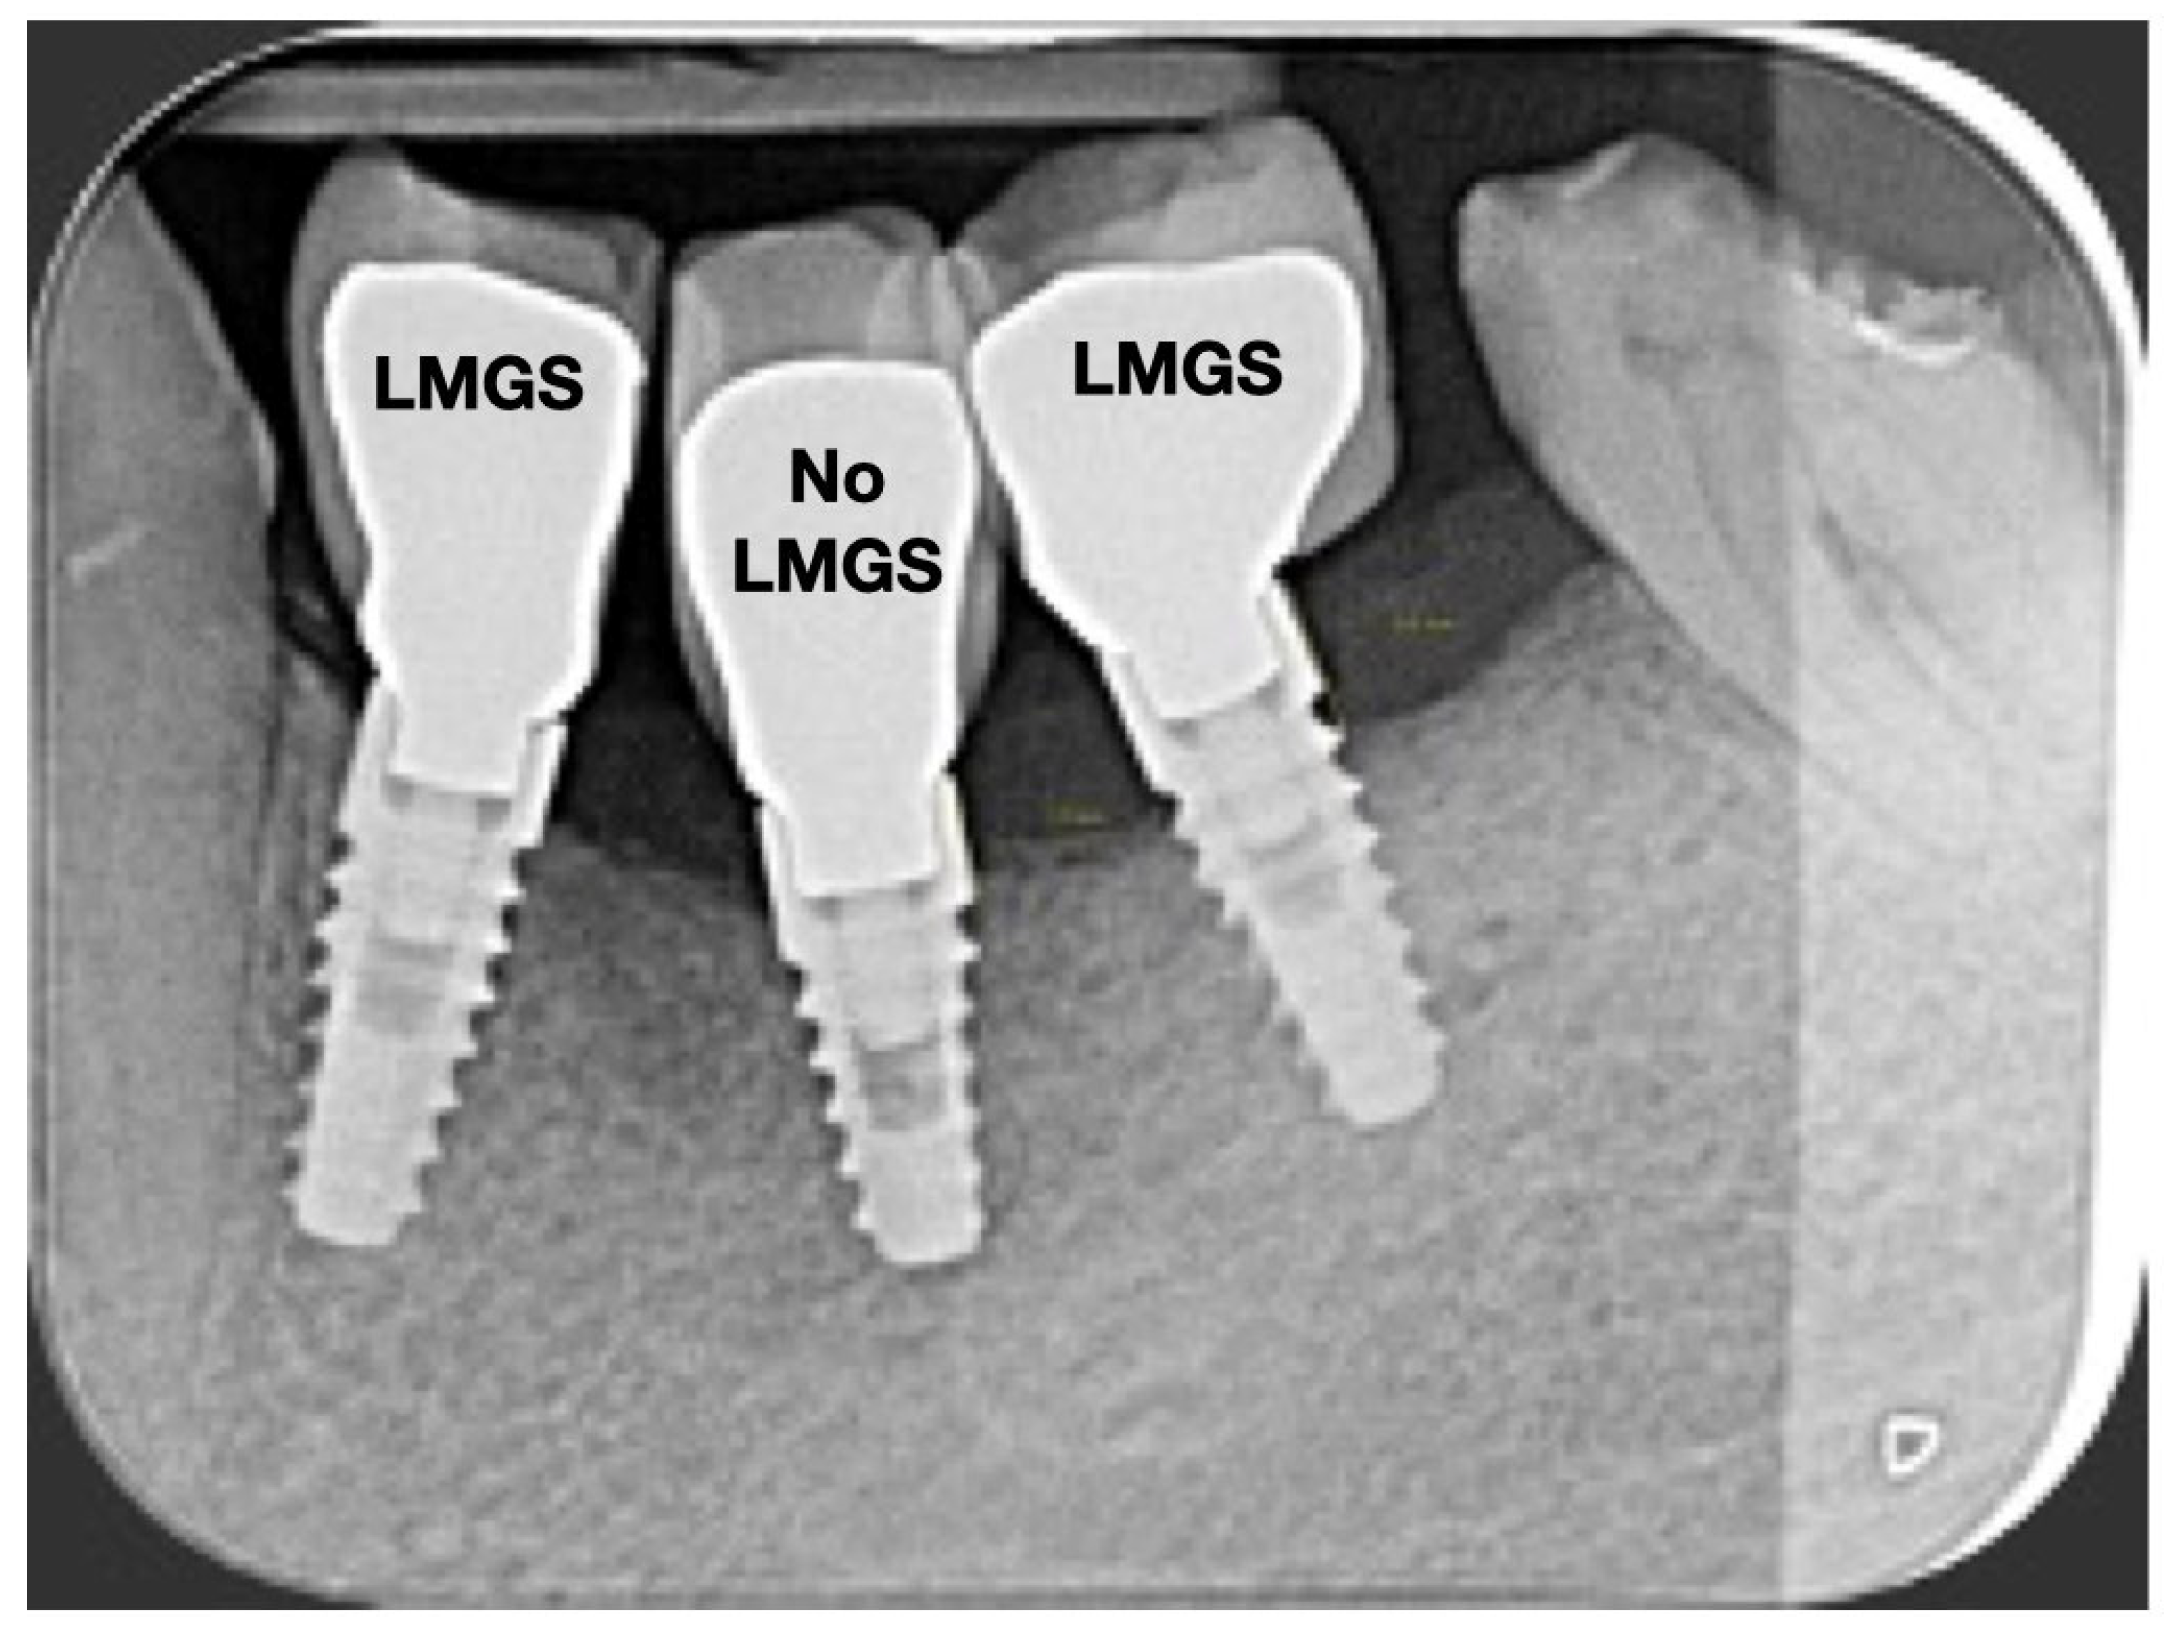

A total of 164 LMGS implants (37.4%) and 195 no-LMGS implants (42.1%) presented PIM. Differences between LMGS implants and no-LMGS implants were not statistically significant (p > 0.05). A total of 28 (6.3%) LMGS implants and 98 (21.1%) no-LMGS implants demonstrated P with a statistically significant difference (p < 0.01). Figure 2, Figure 3, Figure 4 and Figure 5 report examples of radiographs during follow-up.

Figure 4.

Radiograph of the same three (3) implants at 10 years. (LMGS = with a laser-microgrooved collar surface; No-LMGS = without a laser-microgrooved collar surface).